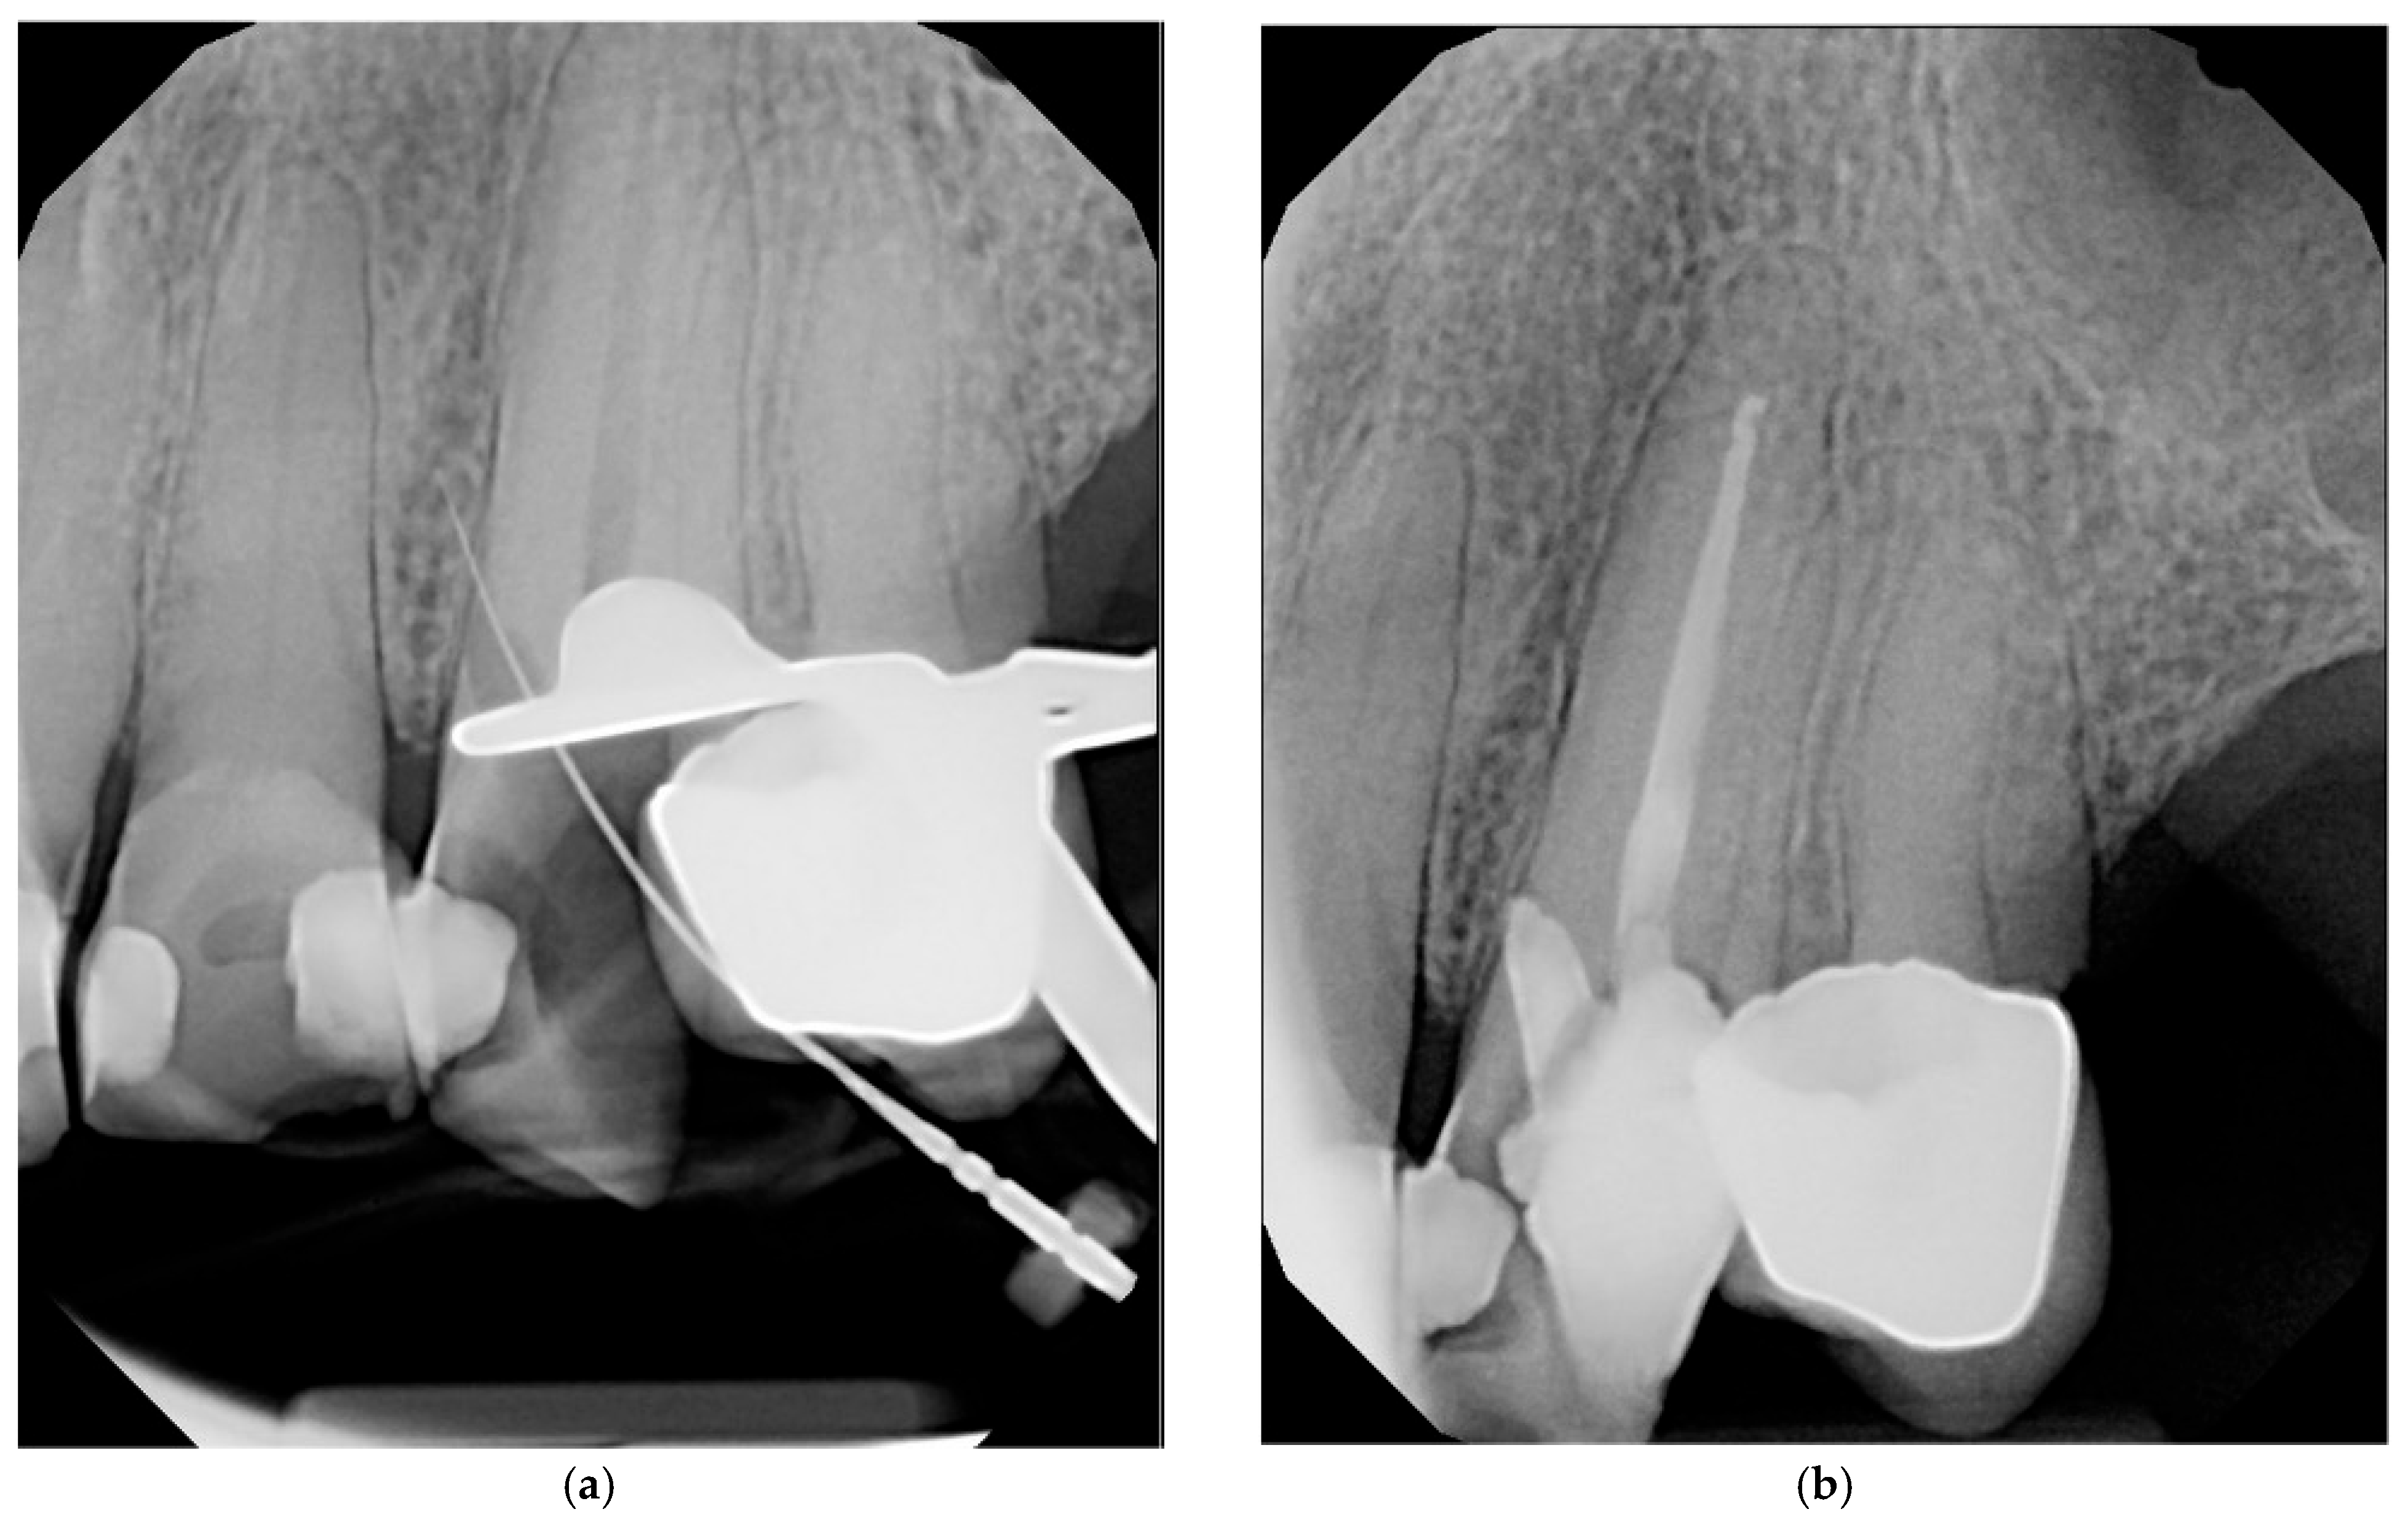

4.8. Management